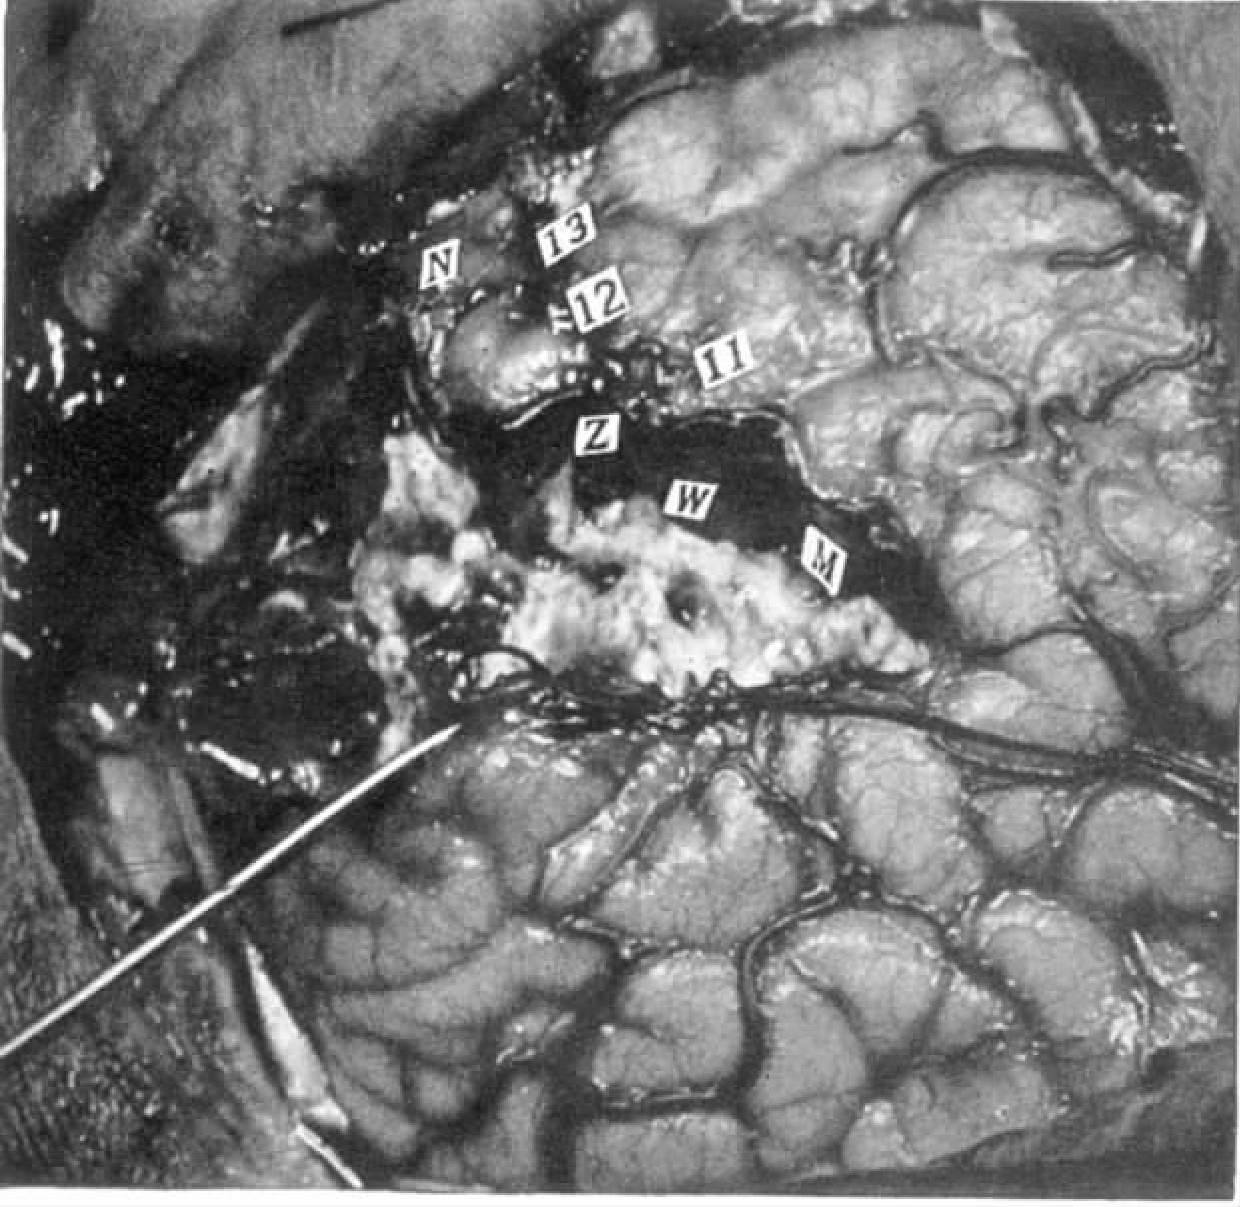

病例3 M.Dr.

患者是14岁男孩,患有继发于右颞叶下方浸润性神经胶质瘤的局灶性皮质癫痫。发作预兆为知觉幻觉。

右脑,近中央沟处的感觉区及次级感觉区(如图4-3)。

图4-3 病例M.Dr.次级感觉反应,也有运动效应

电刺激脑的反应及特点

刺激条件:刺激电流60Hz,强度分别为1V(点1、2、3、5),2V(点7),3V(点8和10)和3.5V(点11和12)。

8 “我的左臂有点感觉。”当被问到是什么样的感觉时,他说:“那仅仅是越过我身体的有点颤抖的感觉。”

8 稍后,重复刺激。患者说:“感觉位于我的左手。”当被问到是什么样的感觉时,他答道:“就像电击,和前一次的感觉差不多。”

8 后来,要求患者用左手进行挤压。当他这么做时,对点8的刺激不影响挤压力度。患者也说刺激时他没有任何感觉。后来,要求他用左手的其他手指依次触碰拇指,当他按要求做时再刺激点8。刺激开始后患者动作显得笨拙,而刺激结束后又恢复了灵活。但此过程中患者自己并没有注意到手部出现任何感觉。

11 左手突然出现运动,手腕伸展,手指屈曲。

11 无提醒重复刺激。患者再次弯曲手指。持续刺激,刺激结束前弯曲的手指松弛下来。

小结

刺激次级感觉区,刺激引起手部的感觉并使复杂的随意运动变得笨拙。刺激点11使手指弯曲。